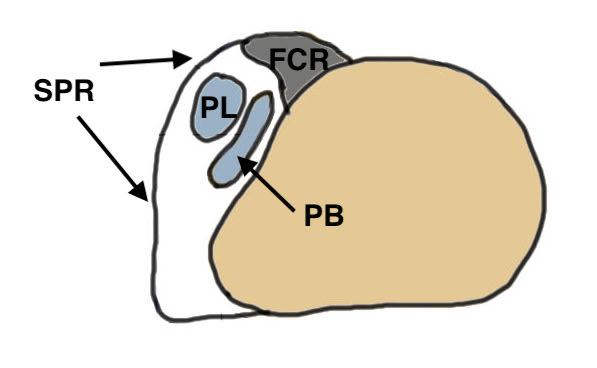

Peroneus longus (PL) posterolateral to Peroneus brevis (PB)

Retro-malleolar groove lined by fibrocartilage |

Fibrocartilaginous ridge (FCR) - on fibula |

1. Injury to superior peroneal retinaculum (SPR) / fibrocartilaginous ridge (FCR)

Peroneal tendons sublux out of grove

| SPR detaches from FCR | SPR and FCR detached | Bony avulsion of SPR and FCR | Midsubstance rupture of SCR |